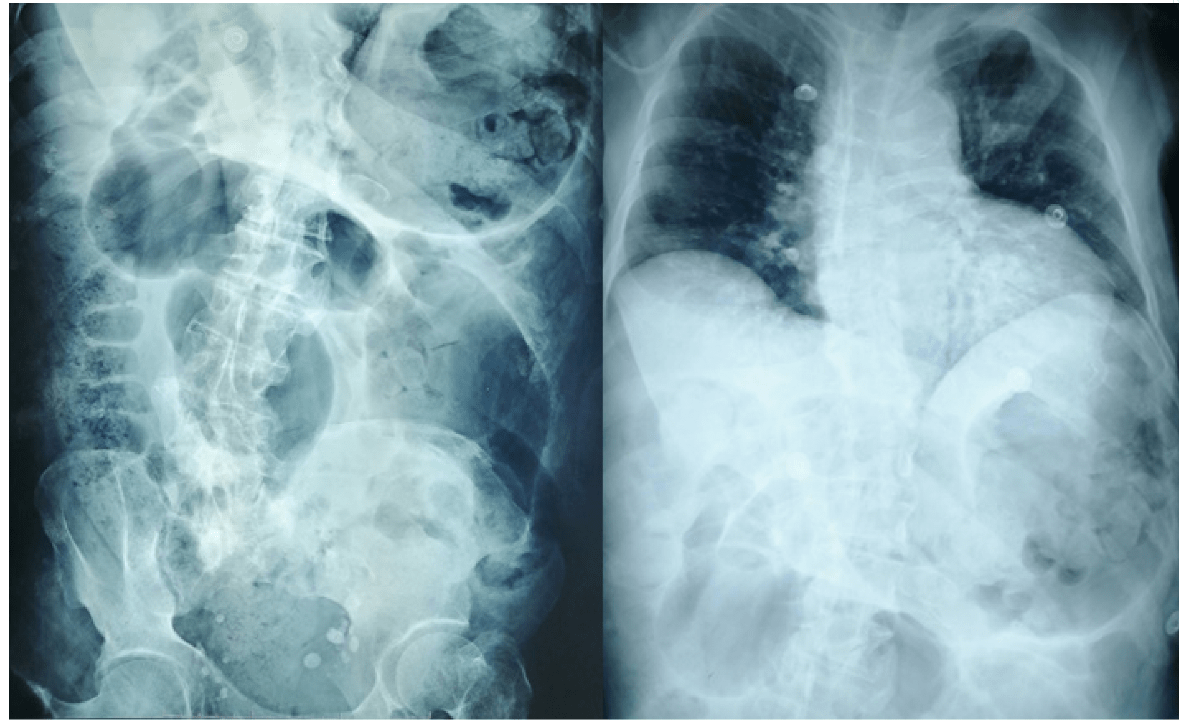

Deciden realizar resonancia magnética abdominal para complementar estudio, la cual se realiza sin administrar material de contraste, lo que limita el valor diagnóstico de la misma pero reportan: en secuencia T1, T2 se observa riñón en herradura aumentado de tamaño con bolsa hidronefrótica que mide 17×13×11 cm, que condiciona desplazamiento anterolateral de asas intestinales, conteniendo material hiperintenso en T2 e hipointenso en T1, con restricción en la difusión con alto coeficiente en ADC con cambios inflamatorios perirrenales (Figura 3) que corresponde a hidronefrosis severa con nivel hidroaéreo más hidrouréter, el cual se extiende hasta unión ureterovesical donde reduce severamente su calibre secundario a engrosamiento concéntrico de la mucosa vesical. Además, reportan rotoescoliosis de convexidad derecha en columna lumbar, lodo biliar, ostomía permeable, líquido libre y gas en cavidad, dato que debió correlacionarse con antecedente quirúrgico de paciente.

Resonancia magnética abdominal

Figura 3